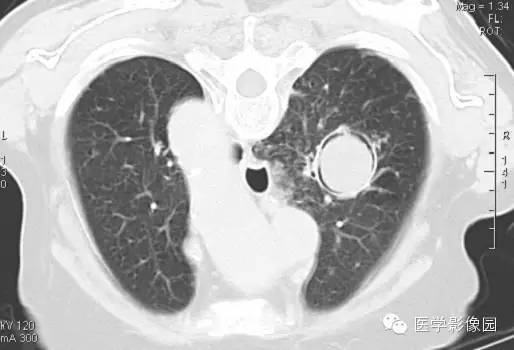

CT表现

右肺内见一圆形空洞病灶,内有圆形曲菌球,边缘光滑,可随体位改变而变动,曲菌球与洞壁之间可见“新月征”。

影像表现为肺内空洞病灶内有圆形软组织密度影,改变体位后曲菌球位置可变动,曲菌球与洞壁见出现一新月形间隙,称为“新月征”。